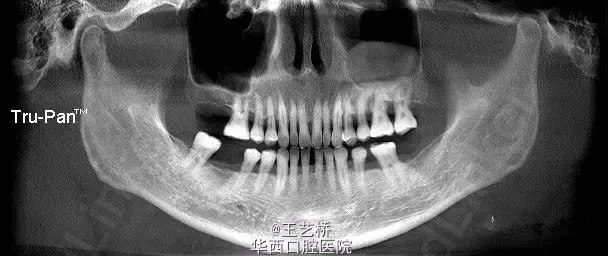

各式各样形态的上颌窦(二)

接着之前放图